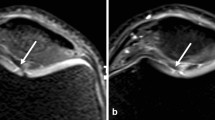

Magnetic resonance imaging (MRI) is crucial for accurately diagnosing a wide spectrum of musculoskeletal conditions due to its superior soft tissue contrast resolution. However, the long acquisition times of traditional two-dimensional (2D) and three-dimensional (3D) fast and turbo spin-echo (TSE) pulse sequences can limit patient access and comfort. Recent technical advancements have introduced acceleration techniques that significantly reduce MRI times for musculoskeletal examinations. Key acceleration methods include parallel imaging (PI), simultaneous multi-slice acquisition (SMS), and compressed sensing (CS), enabling up to eightfold faster scans while maintaining image quality, resolution, and safety standards. These innovations now allow for 3- to 6-fold accelerated clinical musculoskeletal MRI exams, reducing scan times to 4 to 6 min for joints and spine imaging. Evolving deep learning-based image reconstruction promises even faster scans without compromising quality. Current research indicates that combining acceleration techniques, deep learning image reconstruction, and superresolution algorithms will eventually facilitate tenfold accelerated musculoskeletal MRI in routine clinical practice. Such rapid MRI protocols can drastically reduce scan times by 80–90% compared to conventional methods. Implementing these rapid imaging protocols does impact workflow, indirect costs, and workload for MRI technologists and radiologists, which requires careful management. However, the shift from conventional to accelerated, deep learning-based MRI enhances the value of musculoskeletal MRI by improving patient access and comfort and promoting sustainable imaging practices. This article offers a comprehensive overview of the technical aspects, benefits, and challenges of modern accelerated musculoskeletal MRI, guiding radiologists and researchers in this evolving field.